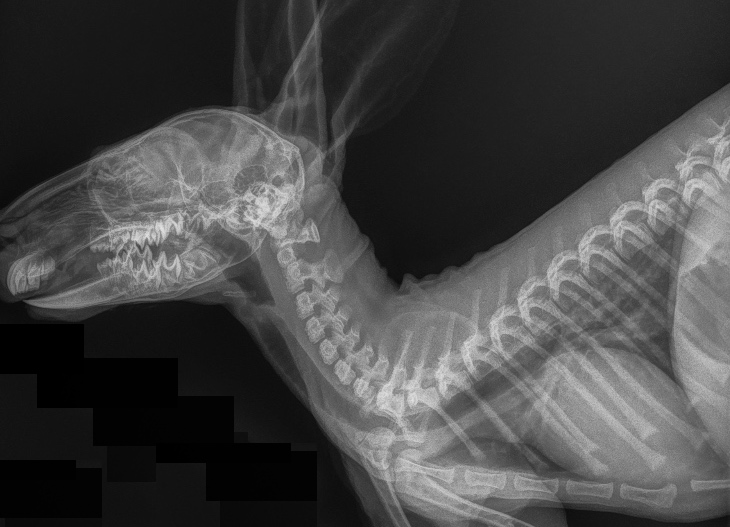

The Whyalla Veterinary Clinic has a new Shimadzu MUX10 Xray machine for high quality radiographs and a new Agfa XD14 Csi Tethered panel to produce outstanding direct digital Xrays from the images from the Shimadzu MUX10 Xray machine.

The XD14 CsI Tethered Panel is an integral part of an Agfa HealthCare’s Instant DR solution, which includes the NX image acquisition software with MUSICA3 processing and detector. These cassette-less and filmless solutions provide a range of workflow benefits that improve quality, productivity and speed up exam time.